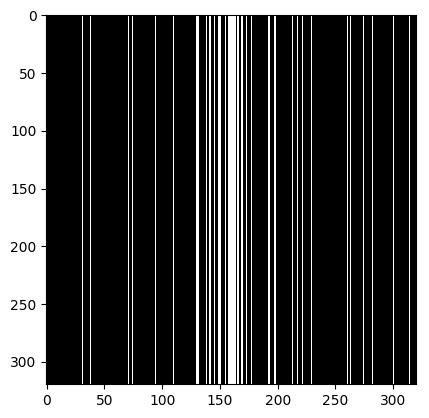

where denotes element-wise (Hadamard) product, and and denote the forward and the inverse Fourier transforms, respectively. The binary matrix denotes the sampling operator that embodies the Cartesian trajectories through which the measurements were obtained; we refer to the rate of decimation induced in -space as the acceleration factor ().

We consider the following two inverse problems: (i) Superresolution (SR), consisting of reconstructing a sharp image from measurements containing only the central low frequencies obtained by using the mask as in Fig. 2 (a & c); and (ii) Dealiasing, in which the obtained mask results in an aliasing artifact due to a coarser sampling in the phase-encoding direction. We use the masks displayed in Fig. 2(b & d). The inverse problem consists of restoring a finer sampling grid in the phase-encoding direction. Throughout the paper, we denote the experiments specifying the task name (one of the two tasks above) and the acceleration factor.